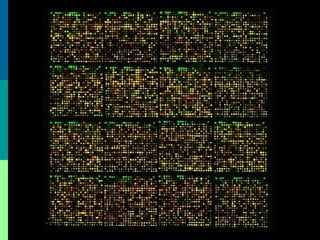

• #41 Precursor T-cell acute lymphoblastic leukemia/lymphoma. Flow cytometry. Staining pattern seen in a marrow cells from a patient with acute lymphoblastic leukemia/lymphoma, precursor T-cell type. The upper left panel shows the pattern of leukocyte common antigen (CD45) versus side-scatter analysis. Lymphoblasts have slightly dimmer CD45 staining than mature lymphocytes but merges with the normal lymphocyte population. The upper middle and upper right panels show that the bright CD45+ population (indicated by R1 and shown in red on gated graphs) contains a subpopulation of cells that are negative for surface CD3 and surface CD19 but co-express CD4 and CD8 (a common thymocyte phenotype). In this case, the CD4+/CD8+ population accounts for approximately 26% of all cells in the marrow. The lower row of dot plots indicates that this population is surface CD3 negative, surface CD5 positive, surface CD7 positive, and co-expresses cytoplasmic CD3 and terminal deoxynucleotidyl transferase (TdT). TdT is a nuclear antigen, but can be assessed by flow cytometry using permeabilization methods that are also used for assessing cytoplasmic marker staining (cellular fixation in formalin, followed by incubation of antibody with cells in a very weak detergent solution).

• #42 Precursor B ALL blasts are positive for TdT, HLA-DR, CD19, and CD79a. Different stages of maturation have been defined as pre-pre-B ALL (pro-B-ALL), common ALL, and pre-B ALL. Whereas pre-pre-B ALL blasts are positive for CD19, CD79a, or CD22, but no other B-cell differentiation antigens, common ALL (cALL, early pre-B-ALL) is characterized by expression of CD10 (common ALL antigen, CALLA), and pre-B-ALL by expression of cytoplasmic immunoglobulins with or without CD10. Mature B-cell ALL (Burkitt's lymphoma) blasts are positive for surface immunoglobulins (sIg, usually IgM), are clonal for or light chains, and are negative for TdT. Similarly to B-lineage ALL, T ALL can be further stratified into subtypes based on different stages of intrathymic differentiation (37,38). Surface CD3 (sCD3) is the most lineage-specific marker for T-cell differentiation and is typically positive in mature T ALL. Mature T ALL is also positive for either CD4 or CD8 but not both. Blasts in pre-T-ALL are negative for sCD3, but may still express cytoplasmic CD3 (39). Pre-T-ALL is negative for both CD4 and CD8. CD52 is expressed in about 30 to 50% of cases of T ALL. It is not lineage-specific, but may have therapeutic significance when using the anti-CD52 monoclonal antibody alemtuzumab. Coexpression of markers from more than one lineage can be demonstrated in 15 to 50% in adult ALL and 5 to 35% in children (40–44). Using flow cytometry, lineage can be assigned in more than 95% of cases and truly biphenotypic leukemias are rare (45,46).

• #43 T(1;19)(Q23;P13.3) oligonucleotide or cDNA microarray technologies are being investigated to identify previously unrecognized molecular ALL subtypes